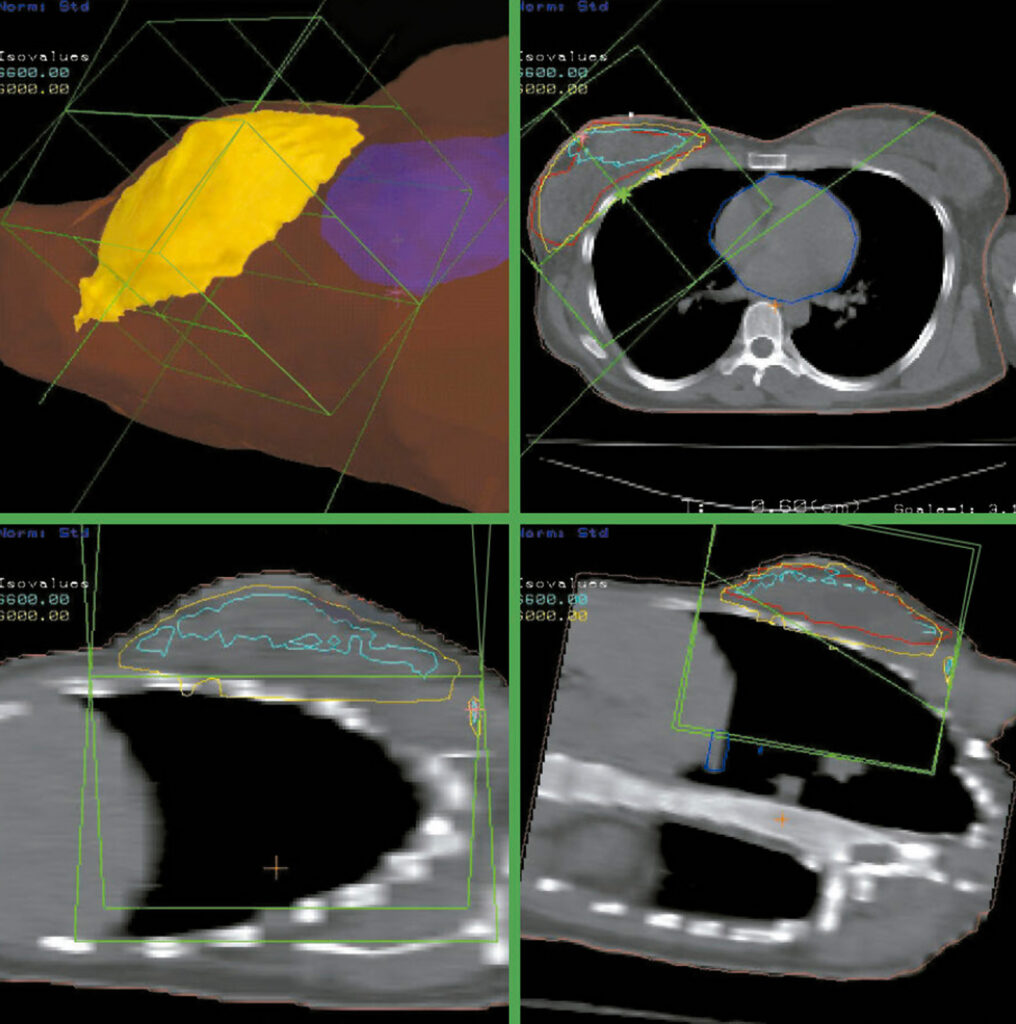

Se adquieren imágenes de TAC y RMN del paciente, que son transferidas digitalmente al sistema IMRT.

Los médicos radioterapeutas delinean los volúmenes de interés, tumor y órganos sanos, definen las funciones objetivos, es decir, establecen las relaciones Dosis-Volumen que desean obtener y adoptan una estrategia de fraccionamiento apropiada. Luego se diseña una configuración de múltiples haces.

Es un avanzado sistema que fusiona información anatómica obtenida de TAC y RMN potenciando la visualización y localización de las estructuras de interés.

IMRT emplea por primera vez en Radioterapia el concepto “Planificación Inversa”, en la cual, a diferencia de métodos anteriores, los médicos prescriben en la etapa inicial cuáles son los resultados deseados en términos de relaciones Dosis-Volumen y la estación de trabajo IMRT converge a la solución propuesta, obteniéndose mapas de campos de intensidades variables mediante un complejo proceso de iteración.